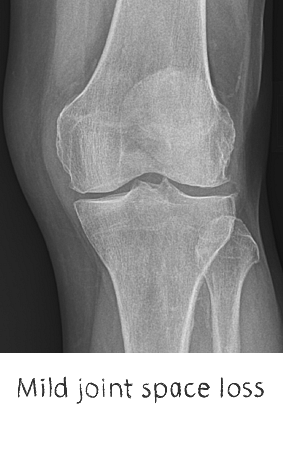

Plain film x-rays are taken to assess the joint

These are usually taken prior to your appointment. These help to confirm the diagnosis, assess the wear pattern and look for particular deformities. They can show old metalware and its position in the bone.